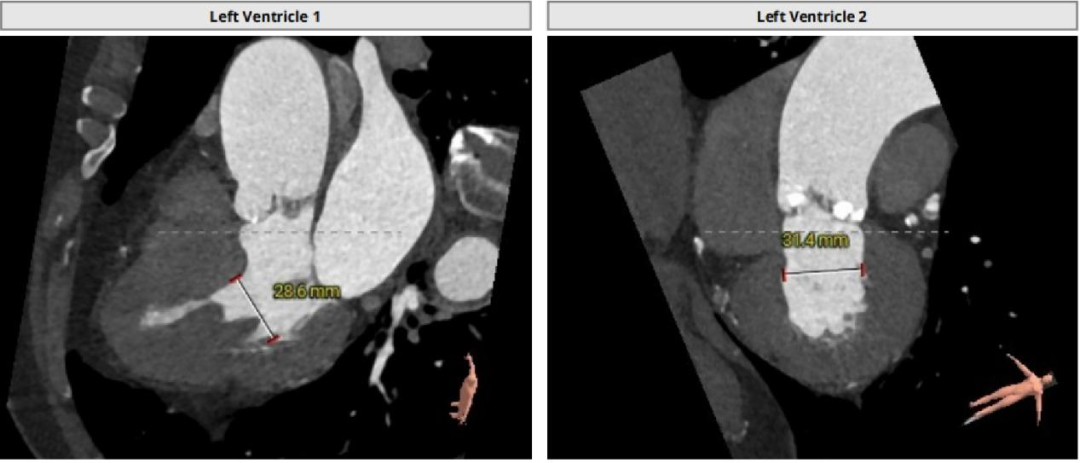

左室腔内径尚可,心室壁增厚明显。